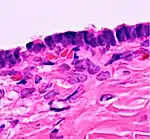

In case an ovarian cyst is surgically removed, a more definite diagnosis can be made by histopathology:

| Type | Subtype | Typical microscopy findings | Image |

| Functional cyst | Follicular cyst |

| Cystadenoma | Serous cystadenoma | Cyst lining consisting of a simple epithelium, whose cells may be either:[21]

|